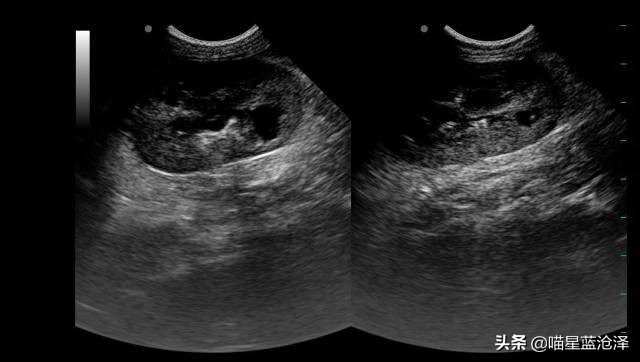

腹部超声:

膀胱可见大量泥沙结石

已存在肾积水

B超可见膀胱明显充盈、膀胱壁增厚,有大量泥沙,典型的膀胱结石诱发的膀胱炎。

肾肾盂光带分离,综合考虑为下泌尿道综合征。